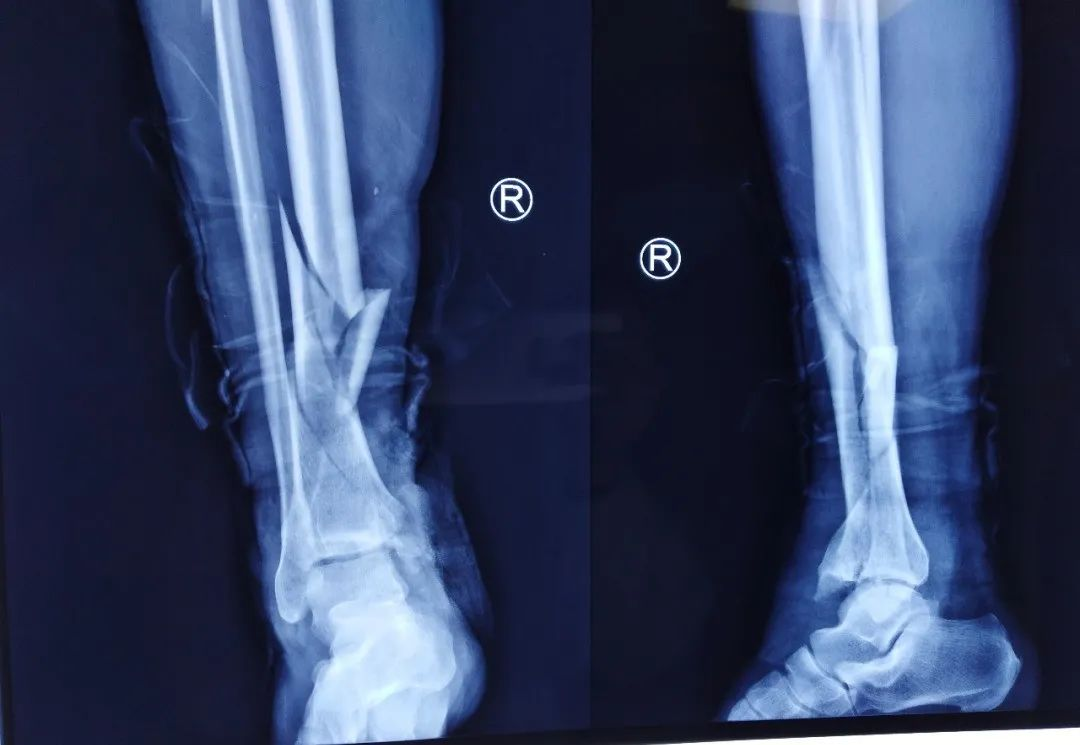

术前平片

患者车祸伤入院,入院查体可见右内踝皮肤缺损面积约5cm*10cm,右足背部皮肤脱套伤,内踝缺如。患者既往高血压、糖尿病,一直服用利血平及阿司匹林。利血平一般建议停用2周,阿司匹林建议停用1周方能进行麻醉。不手术,患者开放性损伤,持续流血状态,失血过多会发生生命危险。手术的话,服用利血平有术中发生血压不能维持,呼吸心跳骤停的风险。

第一次手术拍片